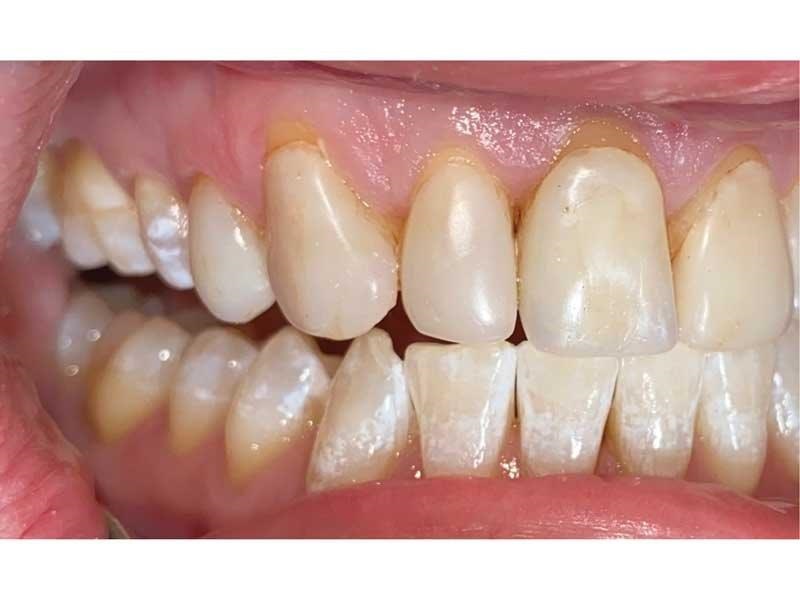

Meet Lorraine, who came into my office to “redo her bonding.” Lorraine had some upper anterior teeth done years ago with resin, which now was dull, stained and breaking down (Figs. 1–3). She had an amount of money in mind that she thought it would cost. She was very wrong.

Fig. 3

Challenge 2: Number of teeth. Lorraine had eight teeth with “bonding” on them, so she assumed we’d be talking about doing eight of something, whether resin or porcelain. But her buccal corridor spaces were dark and suggested narrowed arches, and when I brought that up, Lorraine said she had always wanted a “wider” smile.

The big challenge: Retruded and overclosed. Lorraine looked retruded and overclosed, so I started to ask her about headaches, jaw issues and chronic pain. As we talked, she revealed that she had been in severe pain her whole life. She had all the signs and symptoms of TMD and had been to multiple doctors, pain clinics, alternative medicine practitioners, massage therapists, chiropractors, osteopaths … you name it.